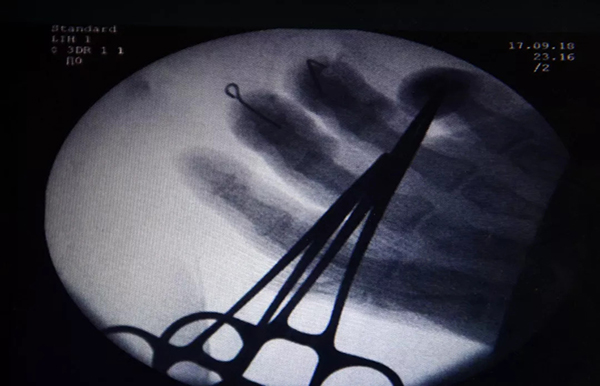

當晚,醫院就給他做了再造重建手術。因為就醫及時,手術情況非常好。醫生説,斷指再造後血液循環很好,色澤也很紅潤,説明恢復良好,一個月後就能痊癒了。

雲南骨科醫院修復重建顯微外科中心二病區主任曹學新説,楊師傅的手術很成功。儘管楊師傅撒尿消毒的土辦法,給他們清創造成了一些困擾外,但勝在他就醫及時。

“本身創口就比較髒,沾了尿液就更加污染了,手術中只有反覆清洗清創,杜絕感染和壞死的發生。”曹學新説,經過手術,他們已將楊師傅手指的骨頭固定,血管和神經重新建立血液循環,現在恢復良好。